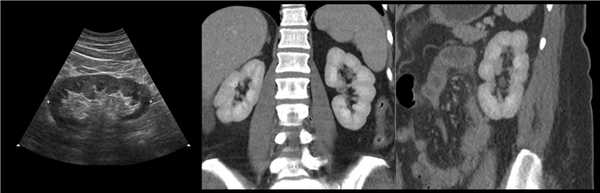

Рисунок. У новорожденного на УЗИ почек определяется гидронефроз (1) и расширенный мочеточник (2) справа. В мочевом пузыре двустороннее уретероцеле (3). При исследовании левой почки структурных изменений не выявлено.

Рисунок. На УЗИ определяется удвоенная чашечно-лоханочная система, расширена лоханка верхнего сегмента (1) и мочеточник на всем протяжение (2, 3), в мочевом пузыре уретроцеле (4). Полное или неполное удвоение чашечно-лоханочной системы возможно увидеть с помощью КТ-урографии.

Рисунок. КТ-урография (1) показывает неполное удвоение ЧЛС слева: два мочеточника соединяются на входе в таз и единым мочеточником вступают в мочевой пузырь; внутрипузырная часть мочеточника расширена (красная стрелка) — уретероцеле. Уретероцеле хорошо видно на рентгенограммах (2) при экскреторной урографии: правый мочеточник расширен на всем протяжении, дистальный отдел кистозно расширен — «голова кобры».

Рисунок. Уретероцеле (стрелка) на УЗИ и КТ.